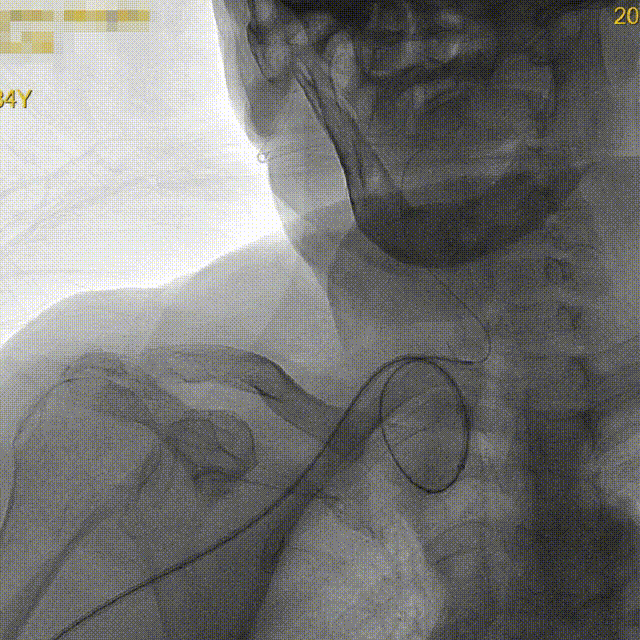

CTA提示右侧颈总动脉迂曲,右锁骨下动脉与右颈总动脉成钝角。

• 颈总动脉迂曲,颈总动脉高位开口,拟经桡动脉建立上肢通路

• 若采用6F长鞘,为避免血管抱死,通常需要RA直径>2.5mm,选择采用5.5F IntroSky X导管鞘可以更好降低并发症风险

• 采用5.5F IntroSky X导管鞘经桡建立通路

泥鳅塑型,携带125cm长SIM2进入右颈总。

5.5F IntroSky X导管鞘顺利绕过迂曲段进入颈总动脉。